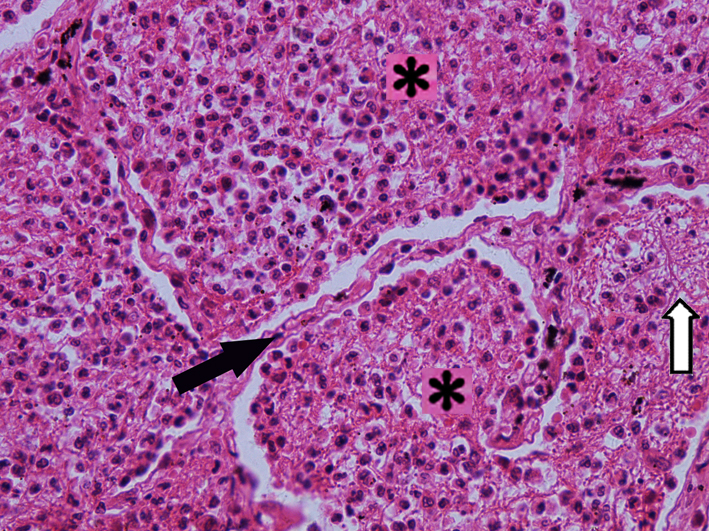

1.大叶性肺炎